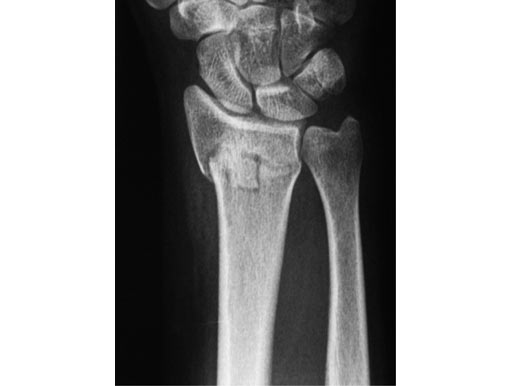

56-year-old female, accident at home